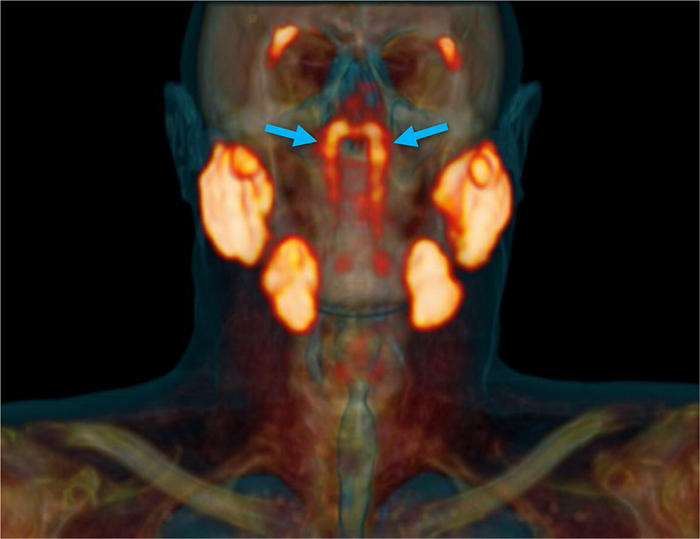

„Непознатиот објект“ бил идентификуван случајно од страна на лекари во Холандија кои испитувале пациенти со рак на простата со напреден скен наречен PSMA PET/CT. Кога ќе се спои со одредени инјекции, оваа алатка за дијагноза ги нагласува туморите во телото. Сепак, во овој случај покажала нешто сосема друго, сместено зад назофаринксот.

Новото откритие на тимот на Вогел е многу поголемо и покажува нешто што изгледа дека е претходно занемарен пар жлезди - наводно четвртиот сет на поголеми плунковни жлезди - лоциран зад носот и над горното непце, во близина на центарот на главата.

- Излезе дека двете нови области имаат и други карактеристики на плунковни жлезди. Ние ги нарекуваме тубаријални жлезди, што се однесува на нивната анатомска локација (над Torus tubarius) - истакнува првиот автор на студијата, оралниот хирург Матијс Валстар од Универзитетот во Амстердам.

Тие жлезди биле забележани во PSMA PET/CT скеновите на сите сто пациенти испитувани во студијата, а и физичкото испитување на два трупа - еден машки и еден женски - исто така ја покажало мистериозната билатерална структура, откривајќи микроскопски видливи канали за дренирање кон ѕидот на назофаринксот.